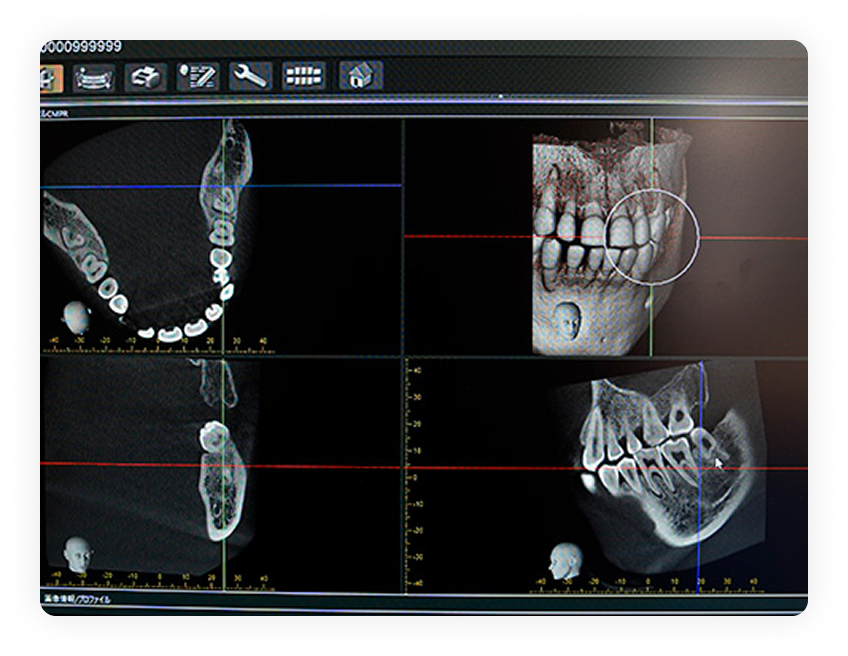

最新設備による

安全な治療

CT撮影や正確な位置にインプラント配置できるサージカルガイドを使用したハイクオリティな治療を行います。 3D画像による精密な診断で治療説明もわかりやすくしています。

精密検査・診断

詳細な問診を通して現在の症状・ご希望をヒアリングします。CT撮影を行い、骨の状態を3D画像で確認。 歯茎の状態や血液検査・心電図を通してお口や身体全体の状態を確認します。コンピューター上で手術シミュレーションを行います。